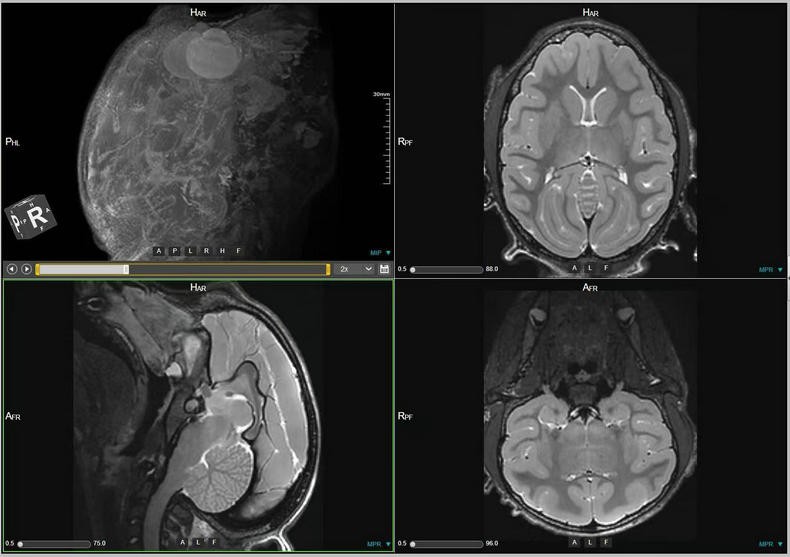

- 关键词:2023-2025年,猕猴,脑部磁共振,3D影像,T1w序列,T2w序列

预定本数据集为2023-2025年对154只0-3岁幼年健康雄性猕猴的脑部磁共振扫描收集的数据,主要包括T1w序列和T2w序列影像(3D影像),对于神经学、心理学、行为学等多个相关学科的研究提供丰富的脑数据支撑。

a.物种:猕猴

b.实验动物信息

样本数量:154只

年龄分布:0-3岁

重量分布:1-6kg

性别分布:雄性154只

c.扫描仪规格

扫描仪类型:联影uMRNX 3.0T磁共振扫描仪器

线圈:12通道猕猴专用头线圈

扫描体位:仰卧头先进

数据采集使用联影uMRNX 3.0T磁共振成像仪器,该设备质量符合国家相关标准,所有设备操作者均接受上岗培训,以确保获得合格的高清晰度图像。